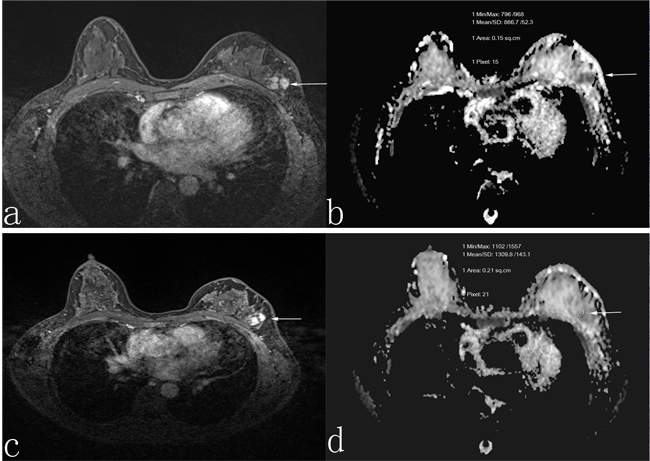

Figure 2: A 45-year-old woman who was non-responder with invasive ductal carcinoma. Before neoadjuvant chemotherapy, the lesion diameter was 3.0 cm in transverse contrast-enhanced T1-weighted image a. the apparent diffusion coefficient (ADC) value was 1.01 × 10-3 mm2/s b. After neoadjuvant chemotherapy, the lesion diameter was 2.8 cm in transverse contrast-enhanced T1-weighted image c., and the ADC value was 1.06 × 10-3 mm2/s d.